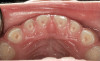

The pattern for bone growth resides not in the bone itself but rather in the soft tissue and muscle that encase the bone.42 Oral-facial muscle tone and tongue tonicity create a framework for normal development of the nasomaxillary complex and mandible.43 SDB is noted in children with pathologic hypotonia of facial and tongue muscles. Children born with a normal palate and oral-facial hypotonia will develop a high, narrow palate over the first year of life (Figure 3 and Figure 4). Children born with a high, narrow palate have hypotonia at birth. These myofunctional changes may be detected in utero.43

(4.) Patient presents bilateral crossbite and significant attrition. Father assists in retraction.

Figure 4